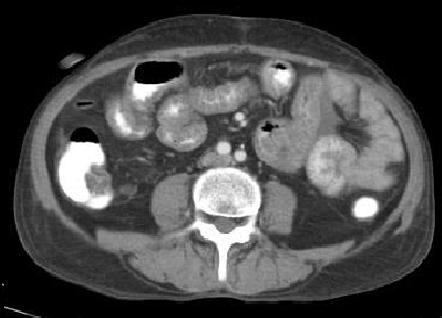

Aspect TDM du tuberculose ileocaecale est : Epaissisement

circumferentiel de la paroi ileum et caecum . Asymetrique

epaissisement de la valve ileocaecale .Mesenteric

lymphadenopathie et tuberculose pulmonaire est le plus

souvent .

Tuberculose ileo-caecale :

Image de epaissisement circumferentiele hyperdense

de ceacum avec lymphadenopathie mesenterique (

fleche rouge ). Image

TDM en coupe coronale |

Aspect de epaissisement

et stenosant de la paroi de ileon dans tuberculose

ileo-caecale( fleche rouge ) Image TDM en coupe axiale |